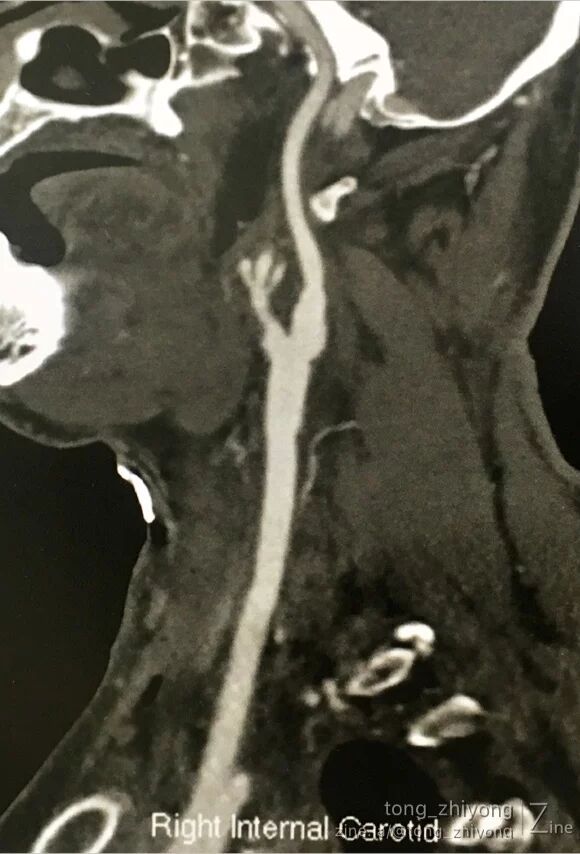

术后一周CTA可见:颈动脉通畅,颈内动脉起始部管径适度增宽。

6. 术后CTA显示:颈内动脉起始部适度增宽。这得益于补片宽度的选择。同时也和术后超声未见涡流信号互相印证;